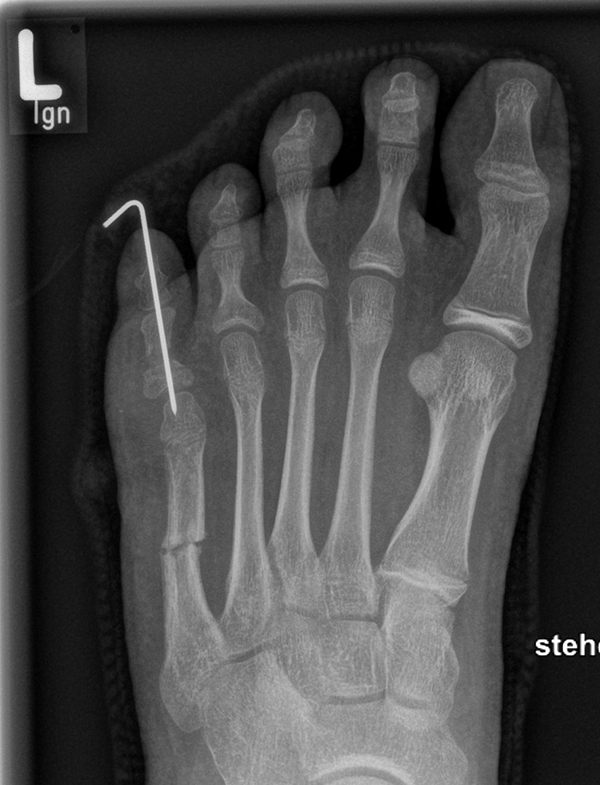

Zusätzlich schränken Wachstumsfugen die Wahl der Osteosynthese ein. Eine die Fuge kreuzende Osteosynthese ist ausschließlich mit Kirschner-Drähten möglich (Abb. 3).

Abb. 3 a-j: Beispiel einer Calcaneusverschiebeosteotomie mit offenen Wachstumsfugen und der entsprechenden Osteosynthese mit Kirschner Drähten. Lokalisation der Osteotomie (a), Lage der Fräse (b-d), Drahtlage mehrere Ansichten (e-h), Heilung der Osteotomie 4 Wochen postoperativ und Entfernung der Drähte (i-j).

Zum Lesen der Bildbeschreibung und zur Vollansicht bitte die Bilder anklicken. Bilder: A. Helmers.